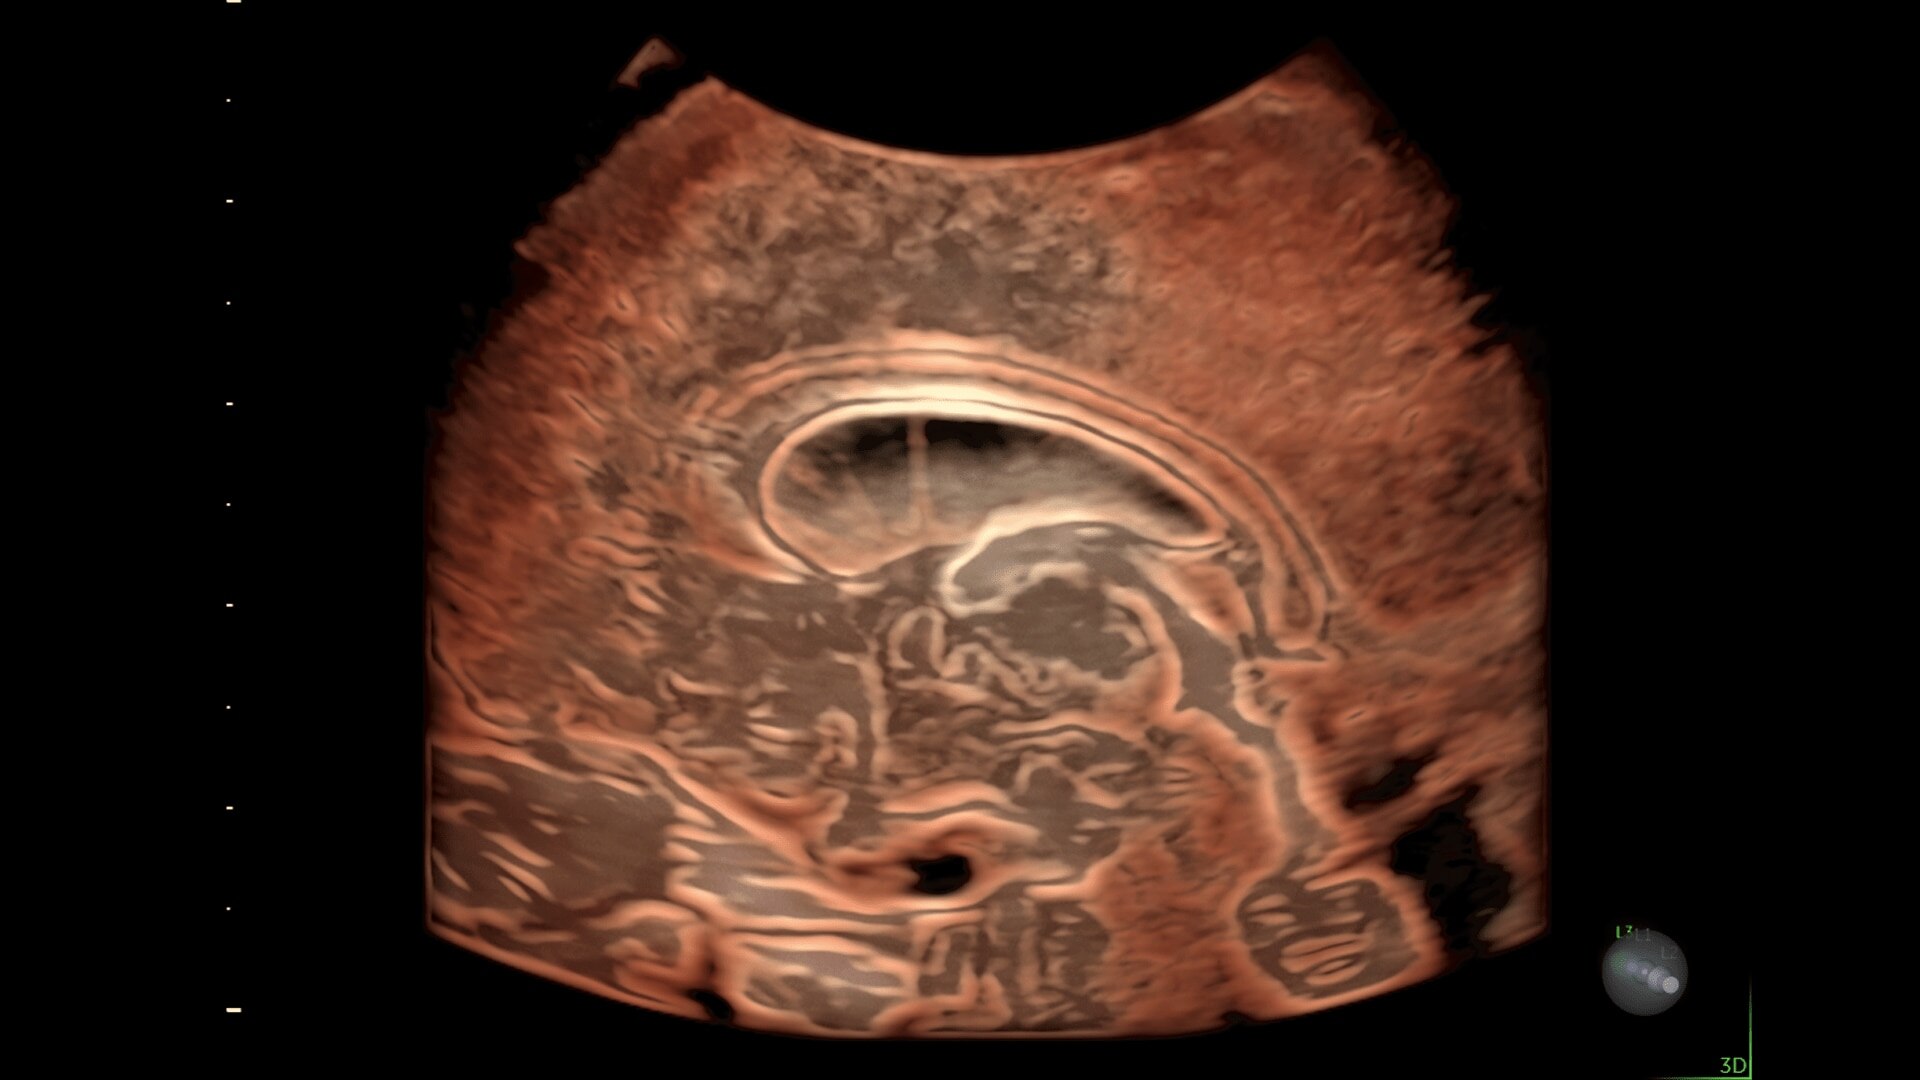

Radiant

Reach New Heights in 2D

Change the levels of elevation and enhance border visibility with Radiant. The result is a more 3D-like appearance, which aids in crucial border differentiation in anatomy such as brain and fetal heart